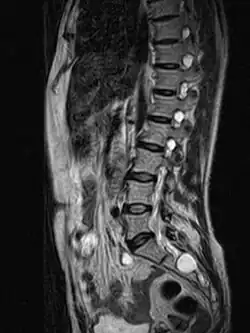

MRI image showing a Tarlov cyst | |

MRI

MRI, or Magnetic Resonance Imaging, is considered the imaging study of choice in identifying Tarlov cysts. MRI provides better resolution of tissue density, absence of bone interference, multiplanar capabilities, and is noninvasive. Plain films may show bony erosion of the spinal canal or of the sacral foramina. On MRI pictures, the signal is the same as the CSF one.